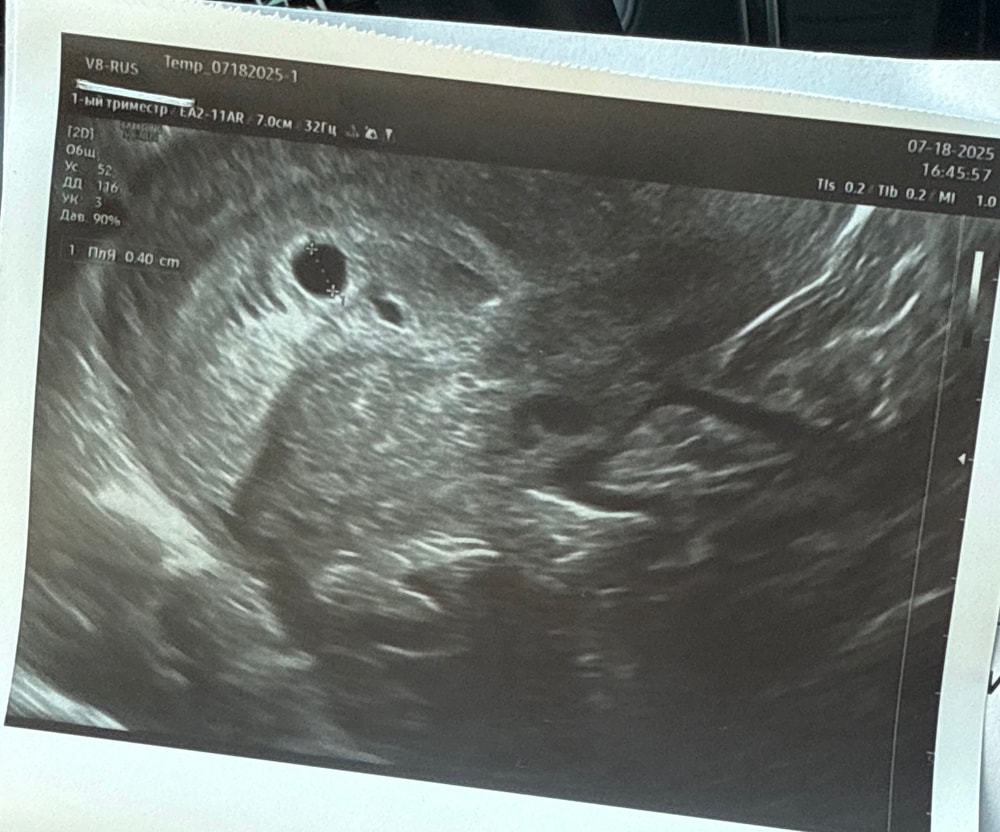

Первое узи 5 недель

Обследования, узи, анализыВсем добрый день! Была на первом узи - плодное яйцо в матке, все отлично. Подскажите, врач ничего не сказала, я по снимку вижу что-то похожее на второй плодное яйцо.. Или это не так?😁 первая беременность, волнительно

У вас одно плодное яйцо на снимке